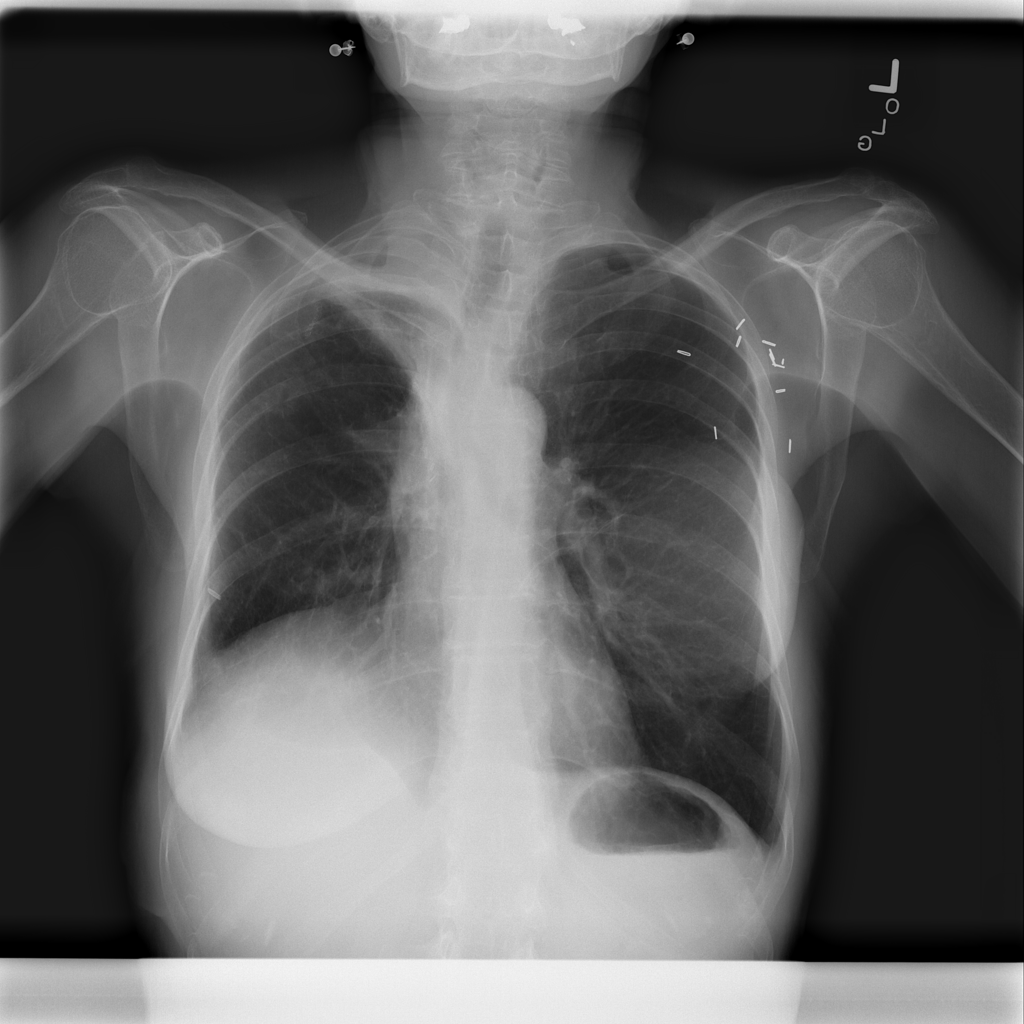

Pneumothorax

Pneumothorax means air is present outside the lung in the pleural space, which can allow part of the lung to collapse. It is an important imaging finding because the size and clinical impact can vary widely.

Showing up to 90 reference images for Pneumothorax.